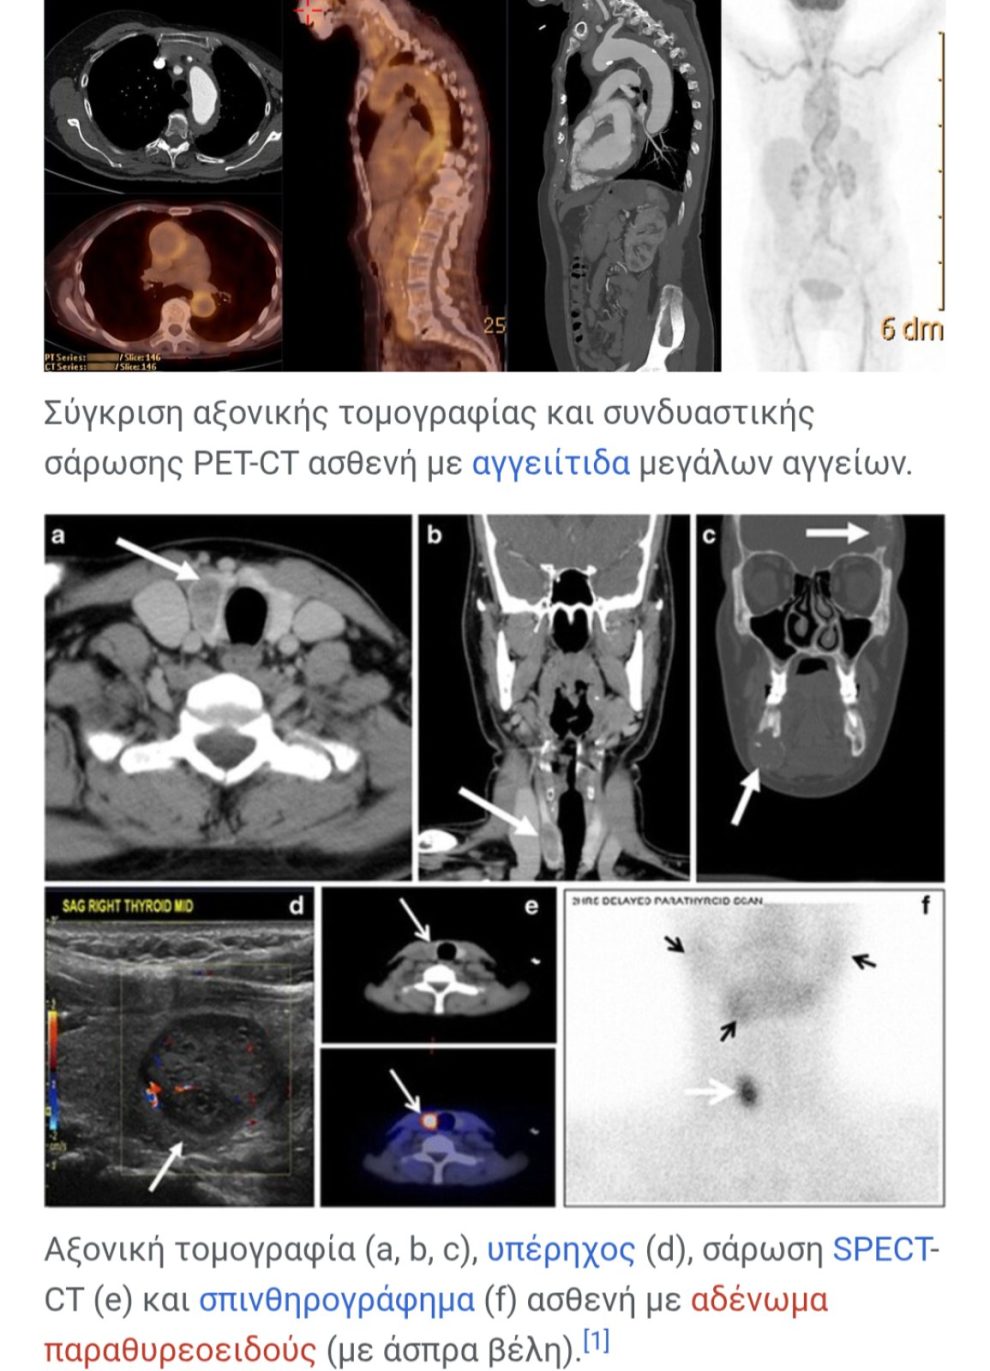

Aξονική τομογραφία (a, b, c), υπέρηχος (d), σάρωση SPECT-CT (e) και σπινθηρογράφημα (f) ασθενή με αδένωμα παραθυρεοειδούς (με άσπρα βέλη).[1]